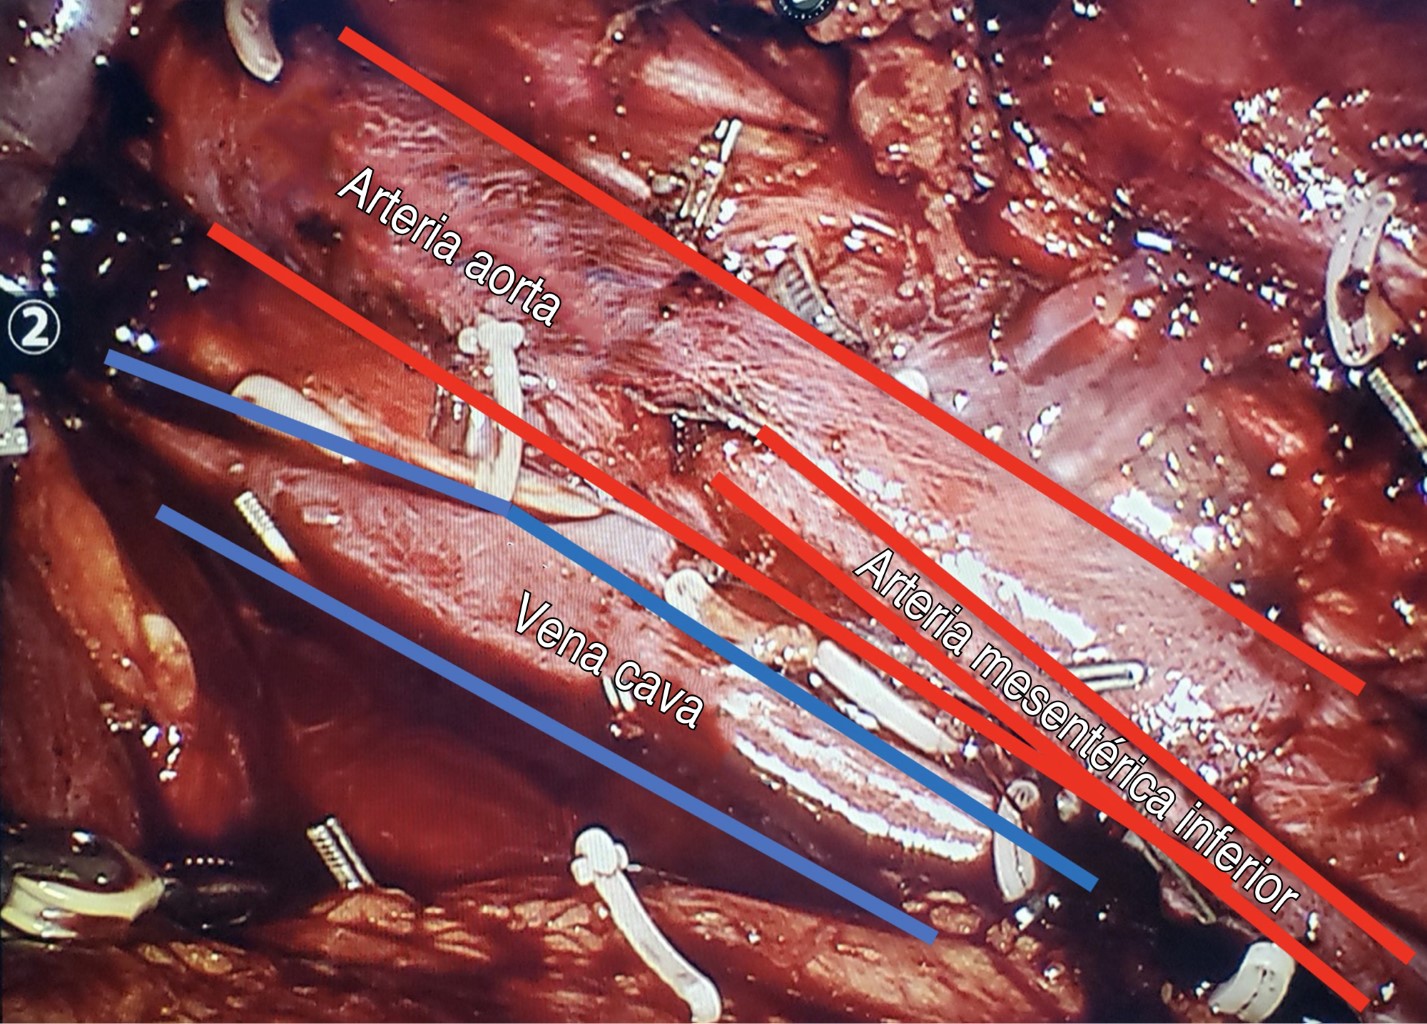

Se comenzó con la incisión de la de línea de Toldt utilizando tijeras con energía monopolar, se movilizó de manera medial el colon descendente desde la flexión esplénica proximalmente y hasta los vasos iliacos de manera distal. Se dividieron los ligamentos colorrenales. Se identificó el uréter izquierdo y la vena gonadal, la cual se siguió hasta el hilio renal. Posteriormente, la vena gonadal se disecó completamente desde su desembocadura a la vena renal hasta el canal inguinal junto con sus linfáticos. Luego, se expuso la aorta y la vena cava inferior, identificando la masa residual a nivel paraaórtico e infrarrenal y disecándola de la aorta (Figura 2).

Se realizó maniobra de split and roll sin evidenciar adherencias importantes, y posteriormente se siguió con la disección de los paquetes ganglionares preaórticos y paraaórticos tomando el uréter izquierdo como el borde lateral de la disección y la vena renal como el límite superior (Figura 3).

Durante la disección se identificaron la arteria espermática y algunas lumbares, las cuales se disecaron, se ligaron con el uso de Hemolocks y se cortaron. Se respetaron las fibras simpáticas superficiales a la aorta, el límite inferior de la disección de dicha zona fue hasta la arteria mesentérica inferior respetando el plexo hipogástrico. Durante la disección se advirtió una lesión vascular en una arteria del psoas la cual se reparó. Cuando se terminó la disección y se corroboró la hemostasia y todas las muestras (resección ganglionar y vena gonadal) se colocaron en una bolsa laparoscópica tipo EndoBag (Figura 4).